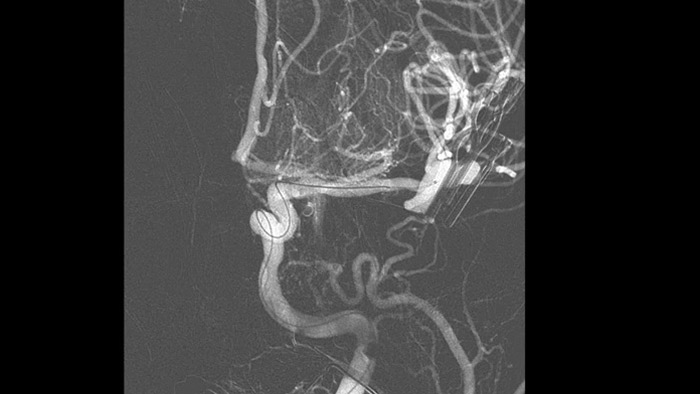

SmartCT Angio — это метод получения рентгеновского снимка, который обеспечивает полную 3D-визуализацию сосудов головного мозга с высоким разрешением с помощью единственной вращательной ангиографии, управляемой с помощью сенсорного экрана у стола. Это может улучшить видимость извилистых или сложных структур, которые, возможно, не видны на изображениях 2D или DSA.

SmartCT Angio за несколько секунд предоставляет объемные данные для просмотра и проведения оценки местоположения, размера, шейки аневризмы и тяжести состояния больного. 3D-объемные изображения визуализируются с высоким пространственным разрешением и автоматической компенсацией движений пациента.